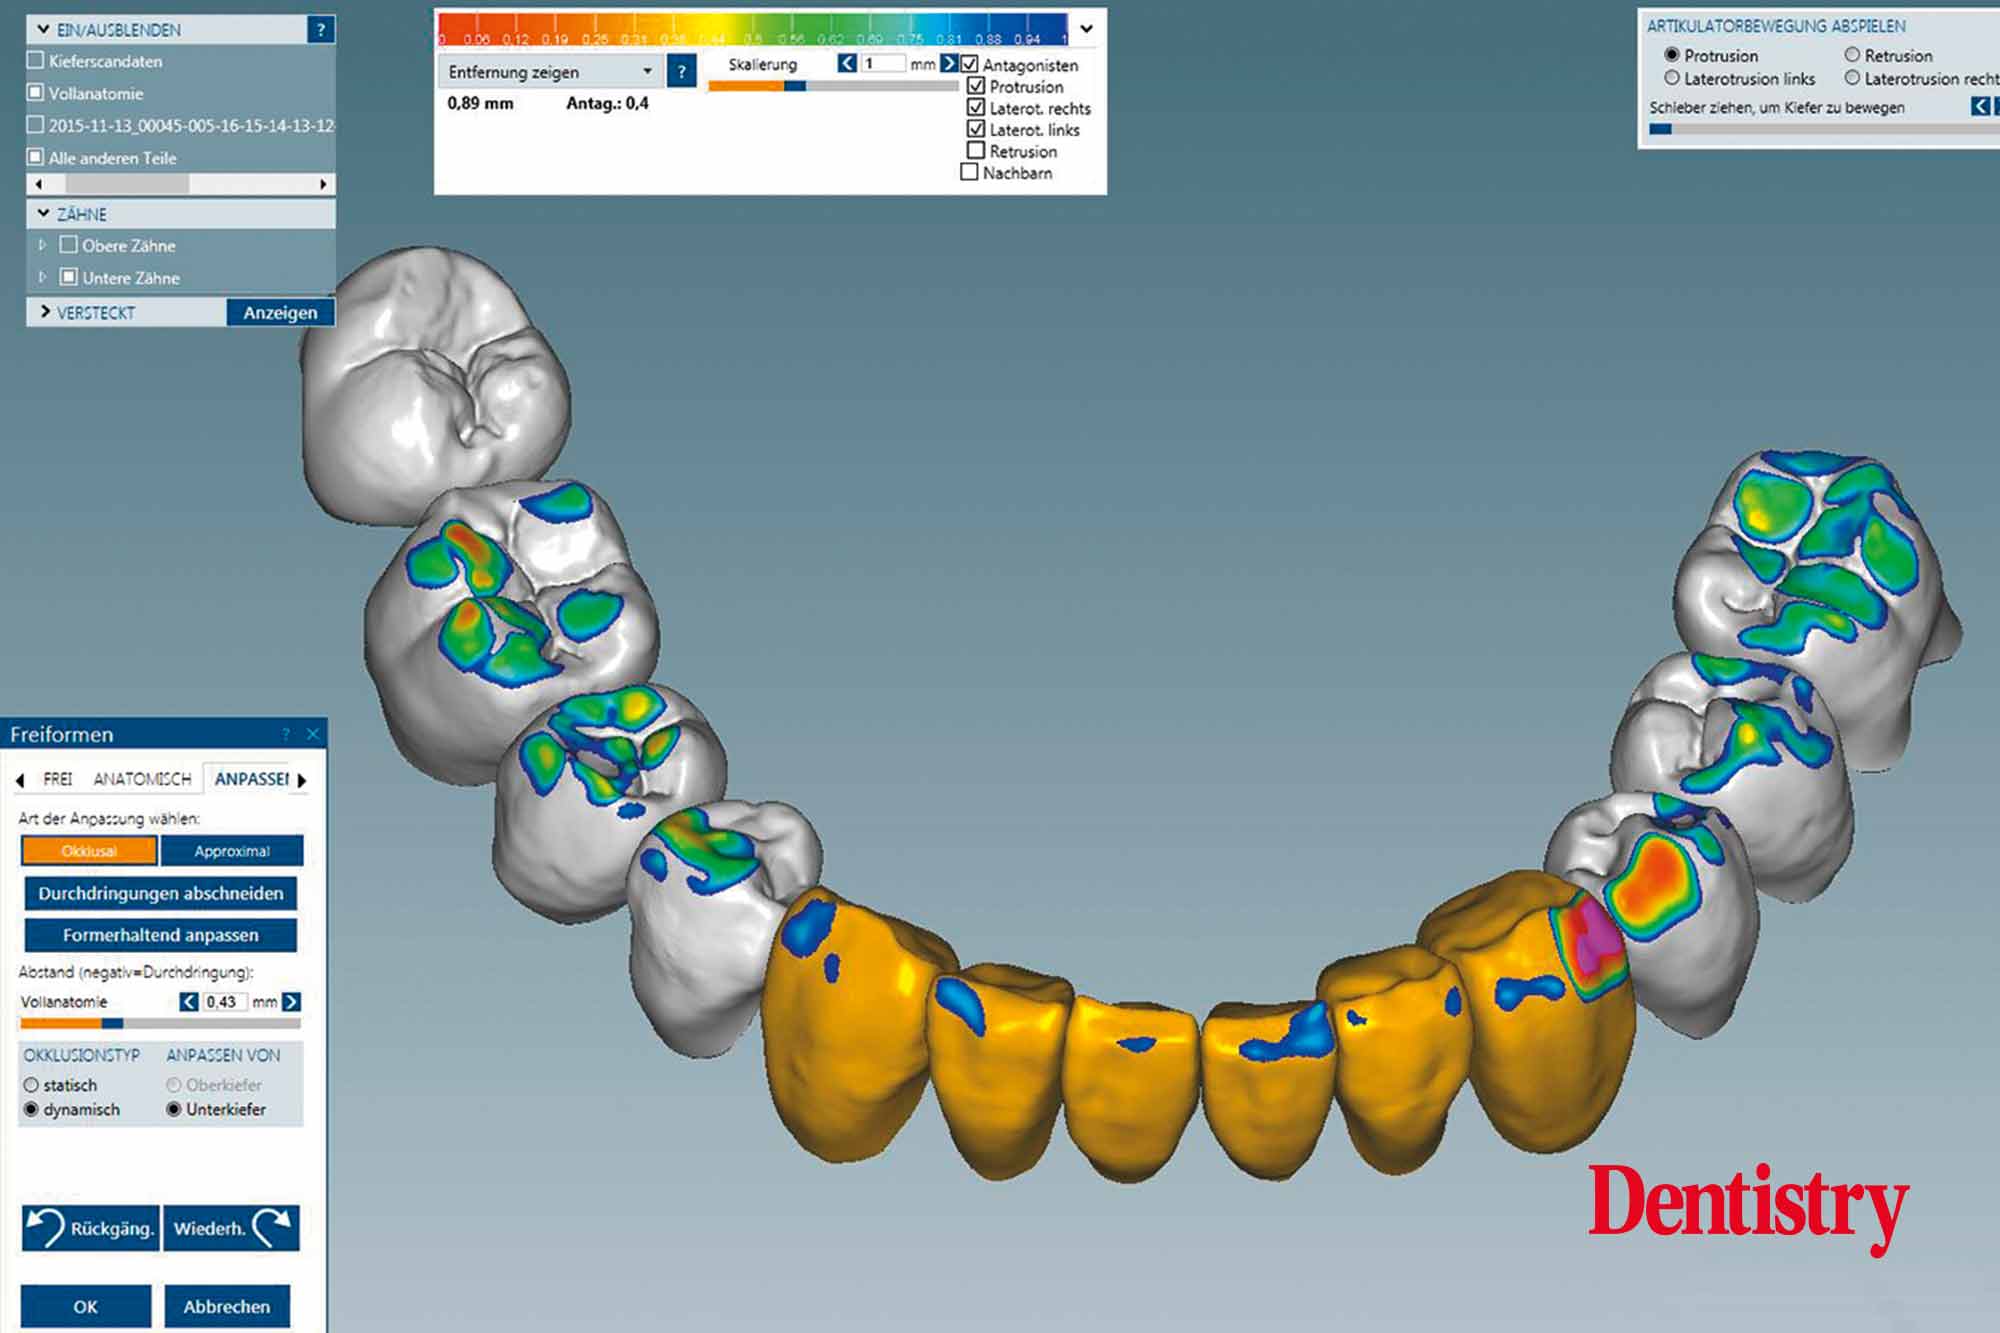

The scanned models were evaluated on a virtual 11 articulator. Temporary Ceramill PMMA (Amann Girrbach) transparent acrylic crowns were CAD planned (Figures 3a to 3d).

Patient data including condylar movements were recorded by the software. Using the Initial situation software’s customised incisal guide unit, the incisal guide pin was adjusted on the splitex plate to the desired cuspal inclinations on the virtual temporary crowns (Figure 4).

All patient parameters including condylar inclination were transferred to the Ceramill Artex articulator and the lateral and protrusive excursions were established while having no contact with the anterior teeth (Figures 5 to 8).